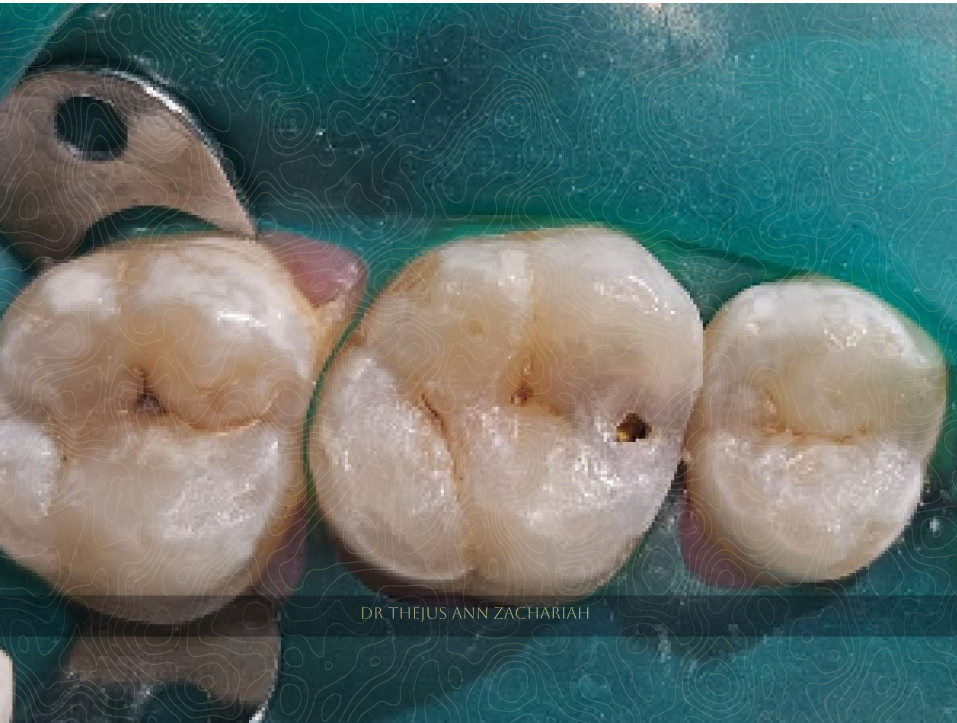

Post-Operative

alt text